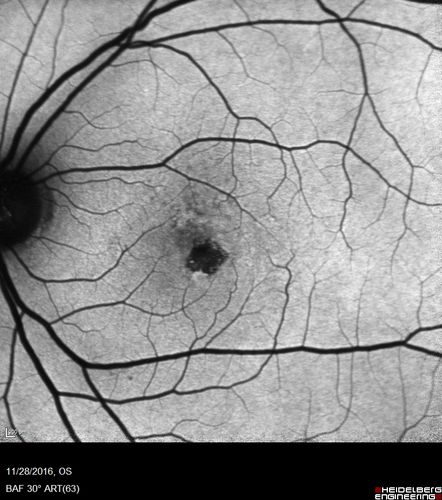

Confluent Soft Drusen with Subetinal Fluid - Right Eye

Asymptomatic 85 year old man.  OCT shows pocket of subfoveal fluid in the center of the macula.  This could be mechanical from the drusen preventing the retina from settling down.  Testing did not reveal a CNVM and subsequent OCT 6 weeks later showed no change in structure.